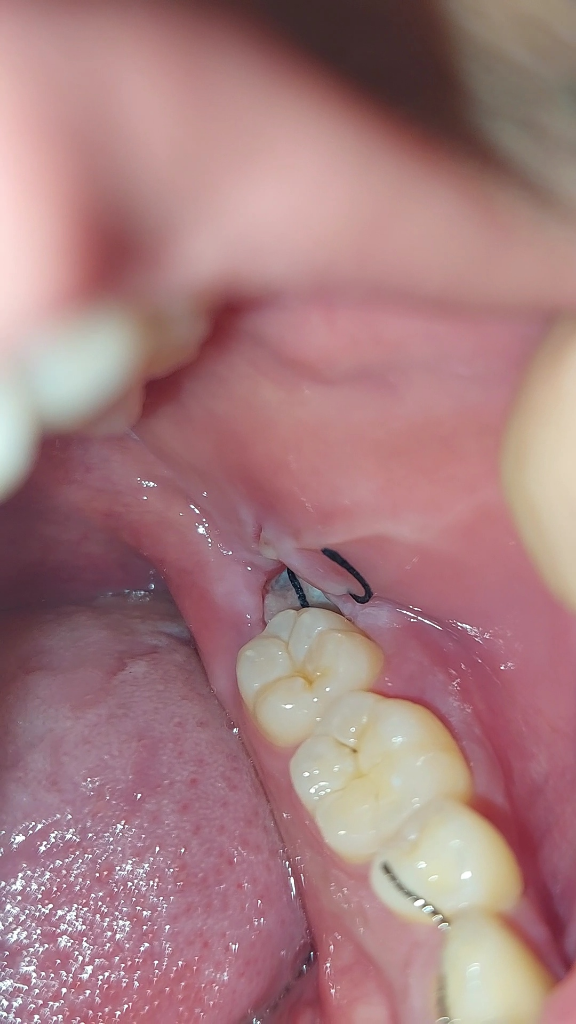

사진에서 정상적으로 아물고 있는 것으로 보입니다. 희게 보이는 것은 주위에 딱지 앉은 것으로 보면 됩니다. 약 먹으면 통증이 없다면 드라이소켓은 아닐 가능성이 높습니다. 드라이 소켓은 진통제 먹어도 아픕니다.

드라이소켓은 발치 후 감염증상으로 굉장히 참기 어려운 통증과 악취를 동반합니다 일단은 사진과, 현재증상으로는 드라이소켓의 가능성은 아주 크진 않습니다 발치 후 2~3일차까지 통증이 있을 수 있고 그 후로는 점차 통증이 완화되며 통증이 있다면 처방받은 진통제를 드시는 것이 좋습니다 5일치 약을 처방받으셨을 것 같은데 남은 약 드시고 발치 후 주의사항 잘 지키시면 됩니다

드라이소켓으로 보이지는 않습니다. 드라이소켓은 통증이 매우 극심하고 냄새도 많이 납니다.

드라이 소켓은 감염의 일종으로 극심한 통증과 냄새가 많이 납니다. 통증이 심하시면 치과에 가셔서 소독을 받으셔야됩니다.